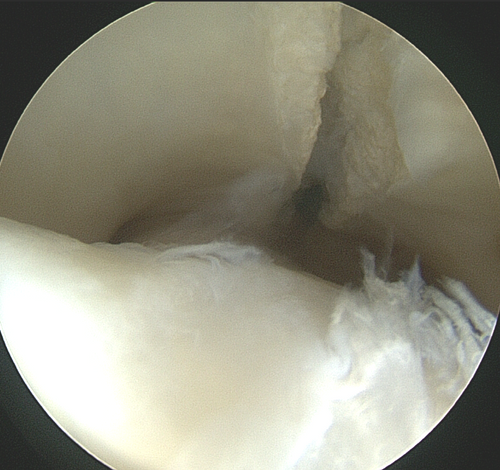

Tendovaginoskopie/Sehnenscheidenspiegelung: Wenn die Sehnenscheide sich entzündet, ist häufig eine Verletzung der entsprechenden Sehne die Ursache. Bei einer Sehnenscheidenspiegelung werden die gerissenen Sehnenfasern entfernt und die Sehnenoberfläche geglättet. Eine intraoperative Behandlung der Sehne kann durchgeführt werden damit die Heilung so schnell wie möglich stattfinden kann. Außerdem kann bei einer Tendovaginoskopie – wenn nötig das Fesselringband oder das Unterstützungsband der oberflächlichen Beugesehne unter Sichtkontrolle durchtrennt werden.